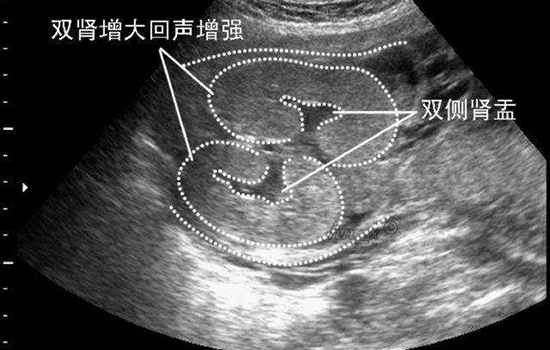

大家都知道,人有两个肾脏,两条输尿管,即有两个肾盂,又称双侧肾盂。而肾盂是肾和输尿管连接的地方,输尿管连接的地方,所以说,肾盂无分离就是指胎儿肾与输尿管的连接处发育正常,是正常健康的表现,无须治疗和担心。

胎儿肾盂分离是比较常见的,肾盂分离是因为胎儿憋尿、肾结石、输尿管畸形等因素导致尿液无法正常排出,于是肾盂被充盈变大形成的。一般来说,如果肾盂分离不超过10mm,是属于正常范围的,如果胎儿出生时不大于16mm,也不会有什么问题,如果继续增大就要定期复查,及时治疗。

若是胎儿憋尿导致的肾盂分离,那么宝宝出生的时候**就没事了,而如果是因为先天尿路(排尿不畅,积压在肾脏里)的问题,那么宝宝出生后就要经过肾盂成形手术才能解决。若是在宫内就比较严重了,那么就得宫内治疗,经**穿刺置入导管减压治疗肾积水。